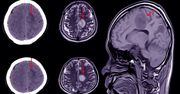

Neurologia to dziedzina medycyny zajmująca się schorzeniami obwodowego i ośrodkowego układu nerwowego. Jest silnie spokrewniona z psychiatrią i polega na odkrywaniu przyczyn uszkodzenia systemu neuronalnego. Domeną psychiatrii są z kolei choroby, których podłoże stanowi biochemiczne zaburzenie funkcjonowania mózgu jako całości. Choroby będące elementem zainteresowania zarówno neurologii, jak i psychiatrii, to m.in.: zespoły otępienne, choroba Parkinsona czy zaburzenia snu.

Zaburzenia neurologiczne mogą wynikać z nieprawidłowości układu nerwowego w wyniku wad genetycznych, uszkodzeń fizycznych z powodu urazów, zatruć lub infekcji, a także w wyniku naturalnego procesu starzenia się. Ośrodkowy układ nerwowy jest chroniony przez bariery fizyczne i chemiczne. Mózg i rdzeń kręgowy otoczone są błonami – oponami mózgowo-rdzeniowymi oraz zamknięte w kościach czaszki i kręgach kręgosłupa. Chociaż nerwy obwodowe zwykle leżą głęboko pod skórą, to za wyjątkiem kilku miejsc, takich jak np. staw łokciowy, są narażone na uszkodzenia fizyczne, które mogą powodować ból, utratę czucia, drętwienie lub utratę kontroli mięśniowej. Uszkodzenie nerwów może być również spowodowane przez obrzęk i siniaki w miejscach, gdzie nerw przechodzi przez ciasne kanały kostne, jak dzieje się np. w zespole cieśni nadgarstka.

Nieuleczalną chorobą neurologiczną jest stwardnienie rozsiane. Dolegliwości początkowo występują przelotnie i są różnorakie. Należą do nich: słabość rąk, drętwienie, drżenie, zaburzenia mowy i wzroku. W wielu przypadkach przebieg schorzenia jest powolny i łagodny – kolejne rzuty przedzielone bywają wieloletnimi przerwami. Stwardnienie rozsiane skutkuje ogromnymi utrudnieniami w wykonywaniu codziennych czynności.

Do innych chorób neurologicznych neurodegeneracyjnych można zaliczyć chorobę Parkinsona, chorobę Alzheimera czy padaczkę.